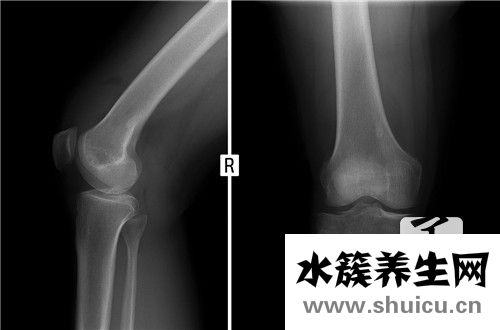

半月板融合屬于一種對關(guān)節(jié)進行整形的人工服務,一般能合理治愈人體關(guān)節(jié)損傷或關(guān)節(jié)位置損傷。半月板融合可以按照手術(shù)的治療方法將人工服務重塑的關(guān)節(jié)嵌入人體,對人體有一定的風險,需要精心治療。通常...